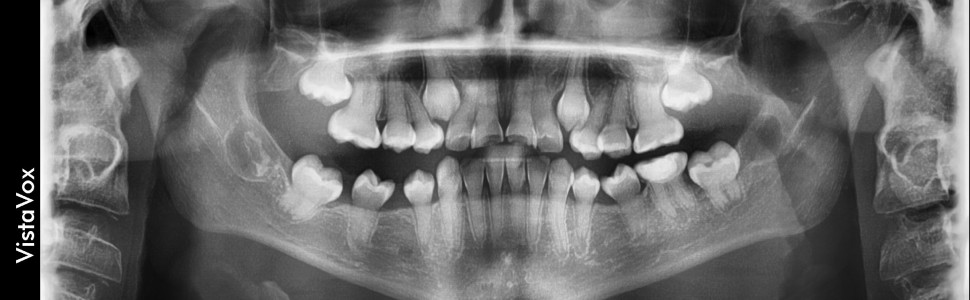

Do wad związanych z niedorozwojem struktur twardych zębów o charakterze dziedzicznym należą niecałkowity rozwój szkliwa (amelogenesis imperfecta) i niecałkowity rozwój zębiny (dentinogenesis imperfecta, odontogenensis imperfecta, choroba Capdeponta). Jednostki te mają charakterystyczne cechy zarówno w obrazie klinicznym, jak i radiologicznym. Diagnostyka obrazowa jest więc nieodzownym elementem w algorytmie postępowania, a opiera się na badaniach konwencjonalnych, tj. zdjęciach wewnątrzustnych i pantomograficznych oraz trójwymiarowych (tomografii stożkowej – CBCT). Daje ona możliwość zaplanowania wieloetapowego leczenia, które powinno być prowadzone przez lekarzy dentystów różnych specjalności. Celem pracy jest przedstawienie charakterystyki tych zaburzeń na podstawie przypadków pacjentów, u których stwierdzono amelogenesis imperfecta oraz dentinogenesis imperfecta.

Disorders associated with congenital hypoplasia of hard tissues of teeth include amelogenesis imperfecta and dentinogenesis imperfecta (odontogenensis imperfecta, Capdepont's disease). These diseases have characteristic features in the clinical and radiological picture. Radiological diagnostics is an indispensable element in the algorithm of treatment. This is based on conventional studies, i.e. intraoral and panoramic radiographs, as well as three-dimensional-studies (cone beam computed tomography – CBCT). Proper diagnostic gives the possibility of planning a multi-stage treatment, which should be carried out by dentists of various specialties. The aim of the study is to present the characteristics of these disorders on the basis of the cases of patients with amelogenesis imperfecta and dentinogenesis imperfecta.